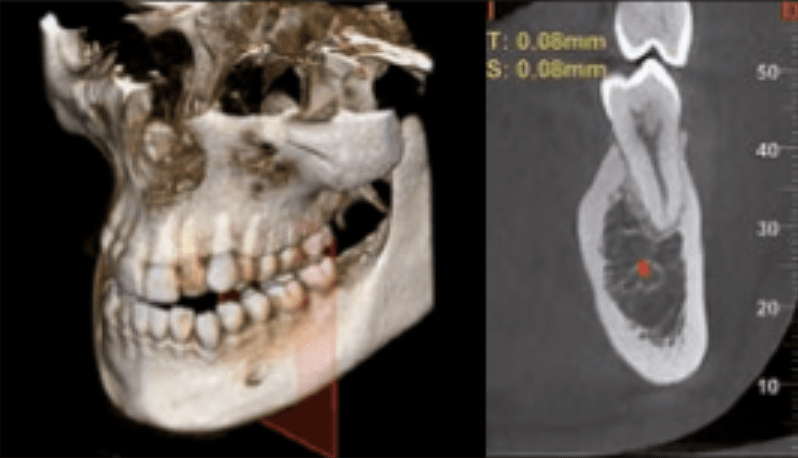

Vrhunska dijagnostika uz CBCT uređaj

Za preciznu i sigurnu stomatološku terapiju, koristimo CBCT – suvremeni uređaj za 3D snimanje koji pruža iznimno detaljan uvid u zube, kosti i okolna tkiva. Ova tehnologija osigurava vrhunsku dijagnostiku i planiranje zahvata, uz minimalnu izloženost zračenju.

- Precizna dijagnostika

- Planiranje implantata

- Minimalno zračenje

- Bolja komunikacija s pacijentom